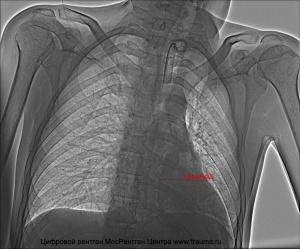

Осмотр проводит травматолог. Сначала врач выясняет обстоятельства травмы и собирает анамнез. Затем выполняет пальпацию поврежденного участка для проверки целостности костных тканей. Инструментальные исследования помогают уточнить или опровергнуть предварительный диагноз. Рентгенография позволяет оценить состояние костей грудной клетки. Магнитно-резонансная томография выявляет повреждения внутренних органов. Компьютерная томография используется для оценки состояния костных структур, если рентген не дал достаточной информации.